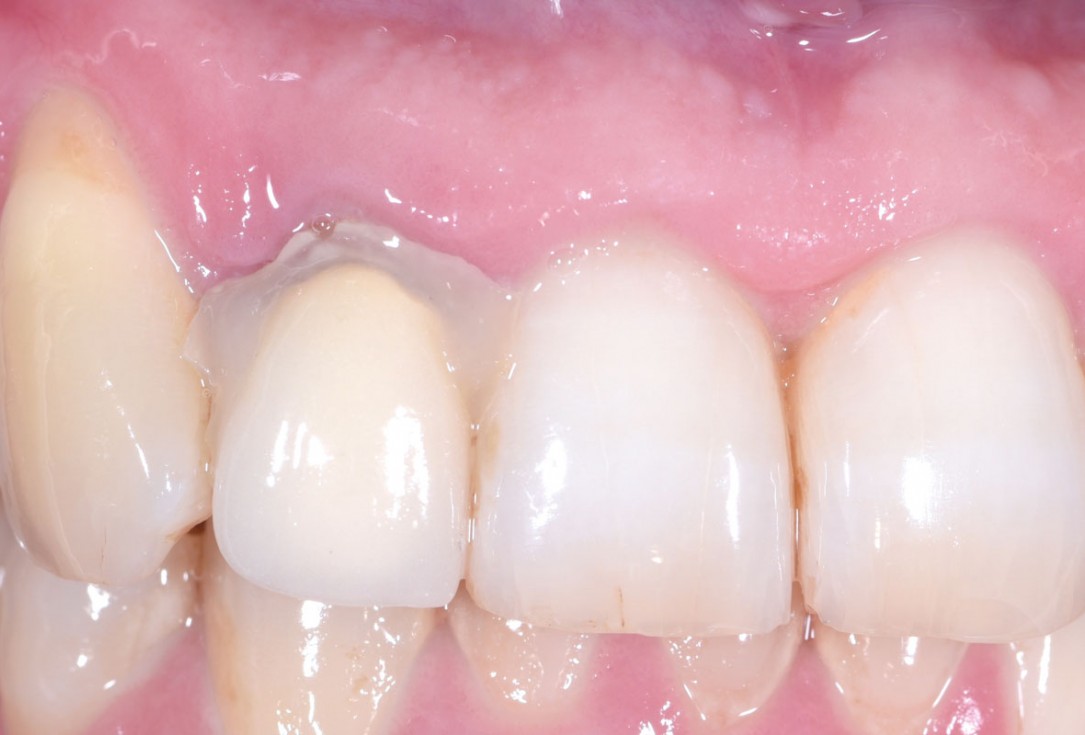

12/13 - Clinical situation 4 months post surgery: Excellent hard and soft tissue adaptation, papilla closing bilaterally

Immediate implant placement in the maxilla with contour GBR - Dr. K. Loukas